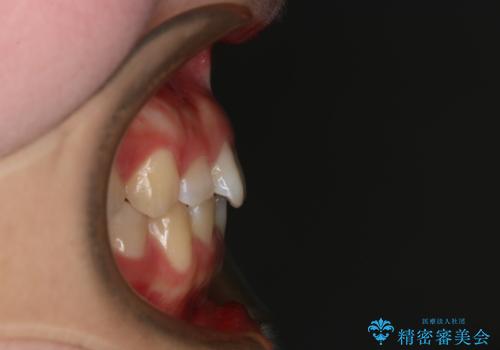

前歯のガタつきを治したい インビザライン・ライトパッケージ

- 前歯のガタつきの改善を主訴に来院された患者様です。

ガタつきによる上顎正中の空隙や歯の突出感も気にされていました。

費用を抑えたいとの事だったので歯の移動量なども考慮し、インビザライン・ライトパッケージでの治療を計画しました。